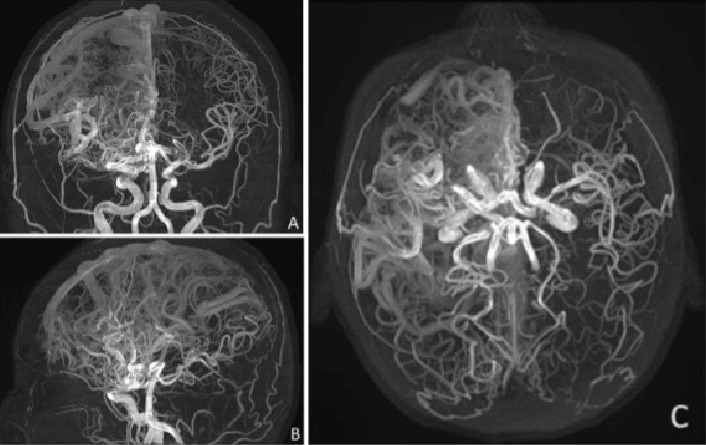

颅内动静脉畸形(AVMs)是一种血管异常,可表现为颅内出血、癫痫发作或神经功能缺损。在本病例中,我们报告了一名6岁时因脑出血而被诊断为巨大右额顶叶AVM (Spetzler-Martin Grade V)的女性。由于病变的大小和明显的位置,手术、血管内和放射外科治疗都不可行。随着时间的推移,患者出现局灶性癫痫发作,包括先天性畸形和左臂痉挛性单眼。最初的抗癫痫药物如卡马西平和苯妥英在最佳剂量下不能提供足够的控制,苯妥英加剧了癫痫发作的频率。通过左乙拉西坦和卡马西平的联合治疗,最终实现了部分癫痫发作的控制。神经影像学显示大的动静脉畸形,脑电图显示局灶性癫痫样活动。这个病例说明了治疗巨大心房动静脉畸形继发癫痫的复杂性,强调了个体化心房动静脉畸形策略和协作、多学科管理的必要性。

Intracranial arteriovenous malformations (AVMs) are vascular anomalies that can present with intracranial hemorrhage, seizures, or neurological deficits. In this case, we present a woman with a giant right frontoparietal AVM (Spetzler-Martin Grade V) initially diagnosed after an intracerebral hemorrhage at Age 6. Surgical, endovascular, and radiosurgical treatments were not viable due to the lesion's size and eloquent location. Over time, the patient developed focal seizures, including catamenial patterns and left-arm spastic monoparesis. Initial antiseizure medications (ASMs) such as carbamazepine and phenytoin failed to provide adequate control at optimal dosage, with phenytoin exacerbating seizure frequency. Partial seizure control was eventually achieved with a combination of levetiracetam and carbamazepine. Neuroimaging showcases a large AVM, while EEG revealed focal epileptiform activity. This case illustrates the complexity of treating epilepsy secondary to giant AVMs, emphasizing the need for individualized ASM strategies and collaborative, multidisciplinary management.